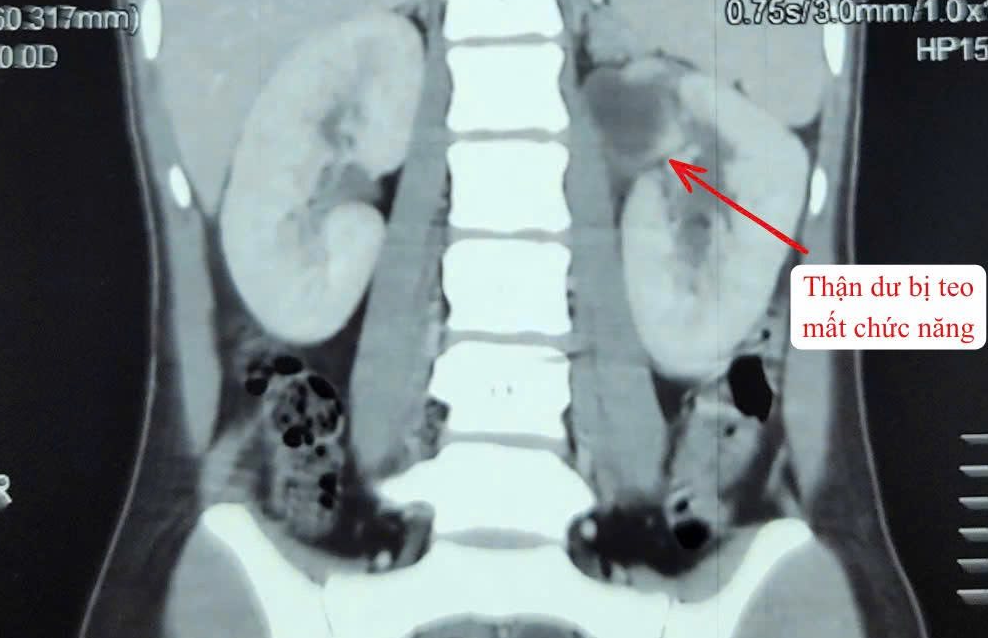

The patient was admitted with high fever and pain in the left flank. Clinical examination and diagnostic tests revealed a rare condition known as a duplicated kidney and ureter system on the left side - resulting in a total of three kidneys.

One of the kidneys had lost function, while the ureter was severely dilated and filled with pus, causing a serious infection.

After multidisciplinary consultation and infection control, the surgical team from the hospital’s urology department decided to remove the entire non-functioning kidney and ureter system on the left side to eliminate the infection source and prevent further complications.